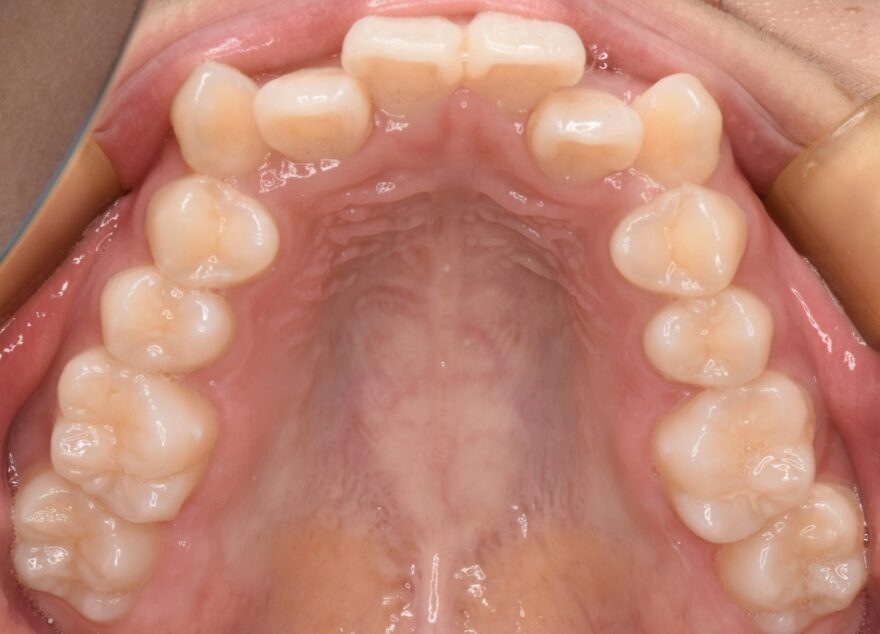

治療後の口腔内写真

約2年の動的期間(歯を動かす時期)で、ここまで整った歯並びになりました。

インビザラインでもワイヤー矯正でも、最終的な仕上がりに差はありません。

八重歯が完全に治りました。

前歯には後戻りを防止するための保定装置を装着しています。